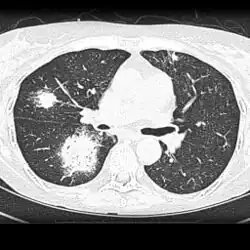

The extent of infection may be seen on X-ray or CT scan. On chest X-ray and CT, pulmonary aspergillosis classically manifests as a halo sign, and later, an air crescent sign.[21]

CT scan lungs: multiple lung lesions with ground-glass opacity suggesting haemorrhage